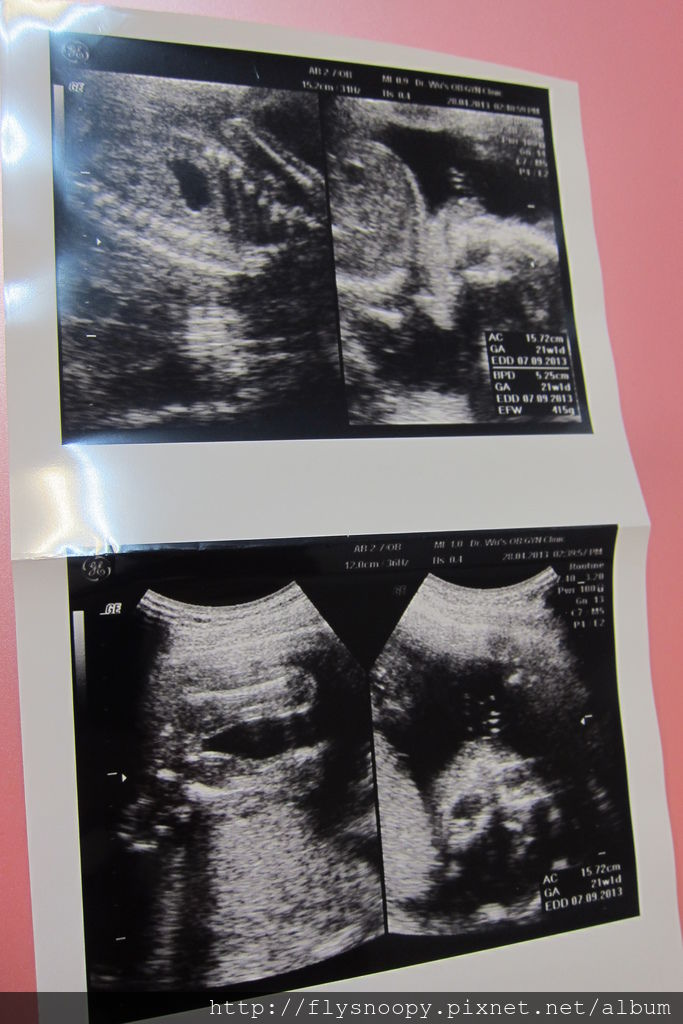

下面是4/24和4/28的超音波照

這三張是4/24照的,第一張看得好清楚,她用手摸頭

這次醫生很確定的告訴我們是個小女生喔